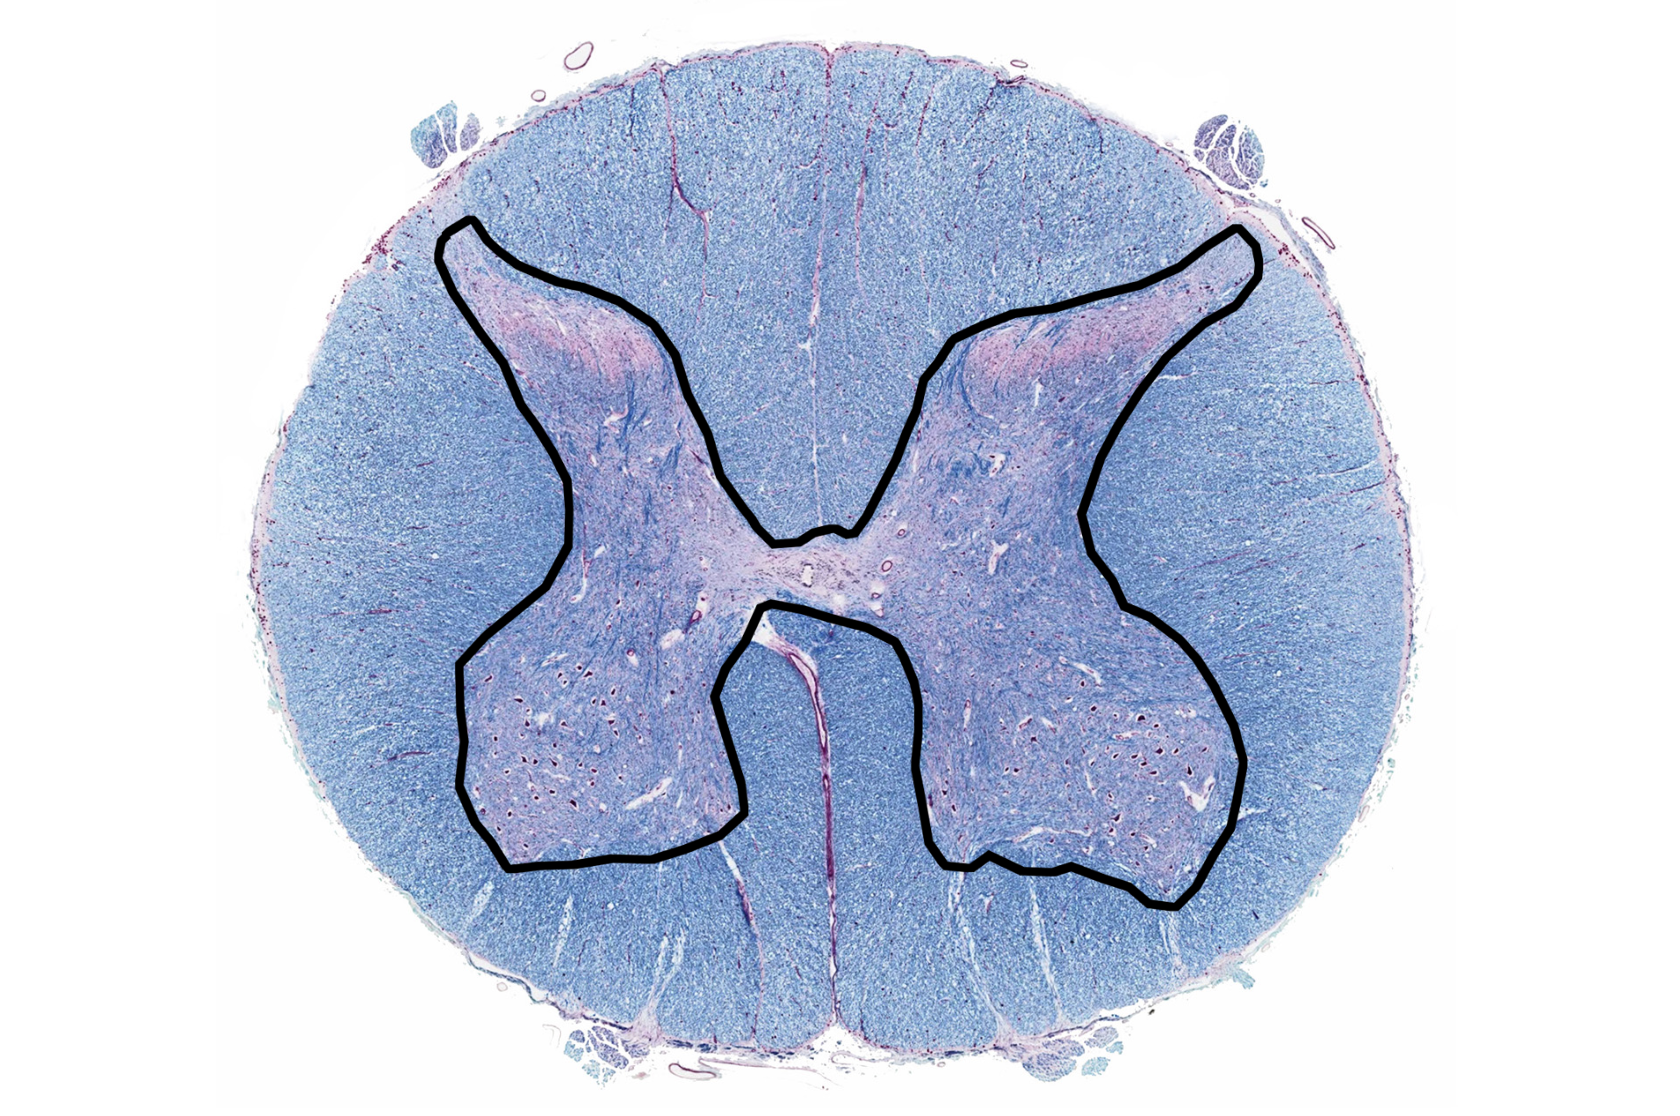

gray matter

posterior horn

anterior horn

lateral horn

gray commissure

central canal